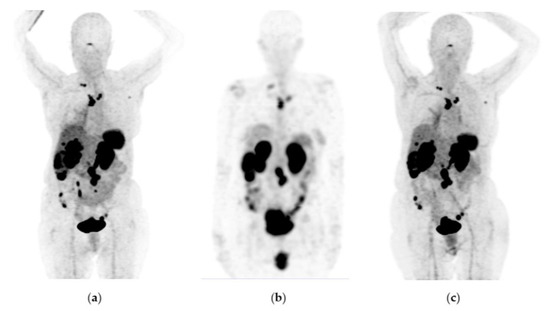

Figure 8. A 76-year-old female patient received four doses of 177Lu-DOTATOC with stable disease as determined by 68Ga-DOTATOC PET/CT imaging. Findings: 11% overall increase in somatostatin receptor expression in the primary pancreatic tumor lesion, as well as metastatic deposits in lymph nodes, liver, and peritoneal implants toward the root of the mesentery, jejunum, and pelvic cavity, without significant morphologic changes. Data refer to a stable disease. (a) 68Ga-DOTATOC PET/CT imaging before 177Lu-DOTATOC therapy, (b) 177Lu-DOTATOC SPECT imaging (first dose), (c) 68Ga-DOTATOC PET/CT imaging ten months after the first dose of 177Lu-DOTATOC.

Figure 6, Figure 7 and Figure 8 show typical clinical cases of partial response and stable disease after 177Lu-DOTATOC therapy (the stable disease does not meet the criteria for partial response or progressive disease).